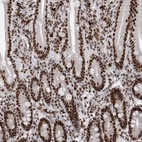

Immunohistochemical staining of human duodenum shows strong nuclear positivity in glandular cells.